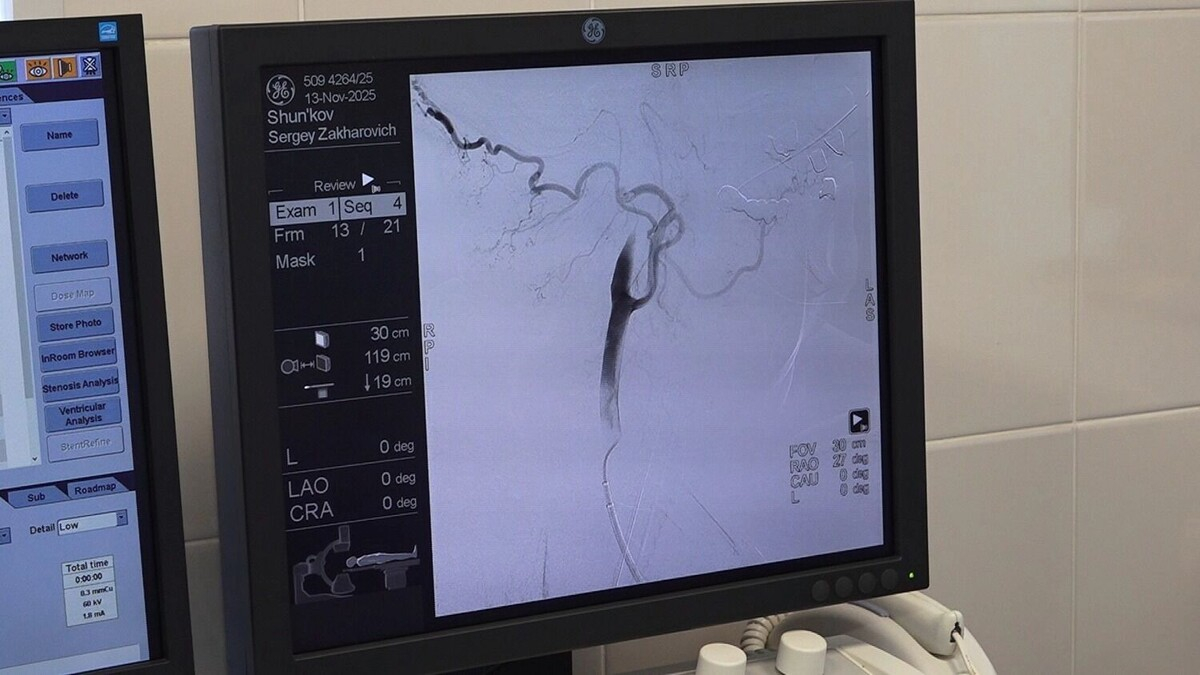

В региональном сосудистом центре городской больницы № 7 в Комсомольске-на-Амуре выполнена первая, в этом лечебном учреждении, церебральная тромбоэкстракция при ишемическом инсульте.

Суть операции в том, чтобы убрать эмбол в сосуде и восстановить кровоток. Для этого, под наркозом, осуществляется прокол в паху, через который вводят катетер. Эта длинная трубка достигает артерии, снабжающей головной мозг кровью, где, с помощью специальных устройств, убирается образовавшийся эмбол.